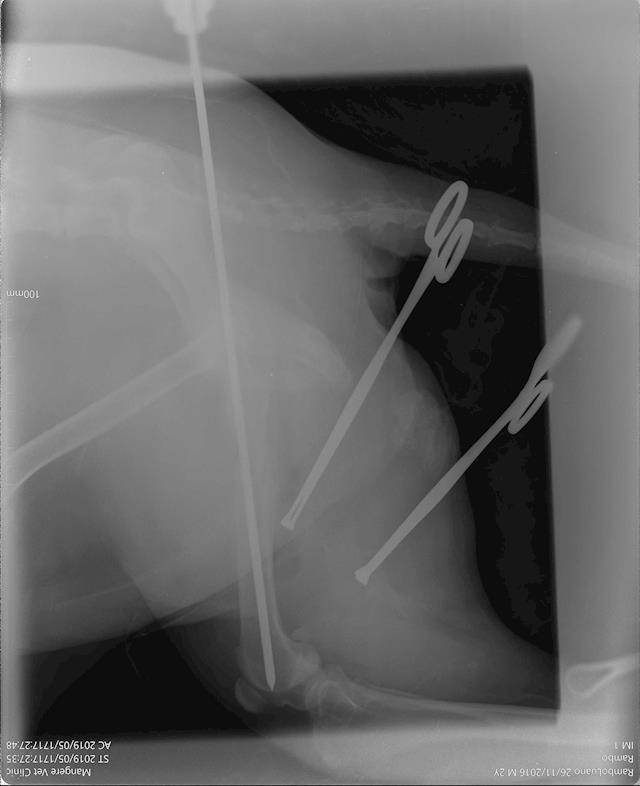

Our Rambo is out of surgery!  18 May 2019

It went really well, I just got off the phone with the amazing team at Mangere Vet Clinic & Onehunga Vet and Pet Supplies who've done a brilliant job of fixing up our Ramby.

The cost of the surgery comes to $1,271.60 so we are very much on track to getting it together and getting him home. Some update pics from the vets 😭🙌 thanks again to every who has donated or shared, it means the world to us and of course to our Rambo (though he may not show it, unless you have treats).